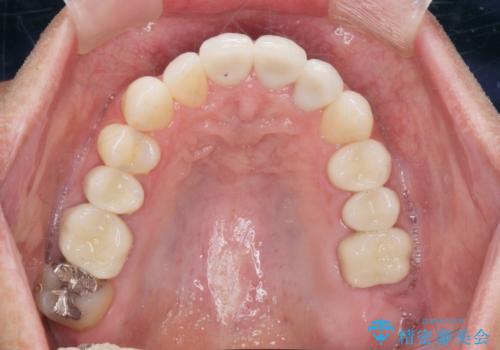

矯正と虫歯のセラミック治療 総合歯科治療の実践

- 突き出た前歯の角度の改善と虫歯治療の改善を求めて来院されました。

虫歯を除去したのち、マウスピース矯正治療を行い、歯並びやがたつきを改善したのち、セラミックに置き換えることで審美性の向上を計画します。

矯正や虫歯治療、セラミック治療といった複合的な治療を一医院で行うことができるのが当法人の大きな特長です。